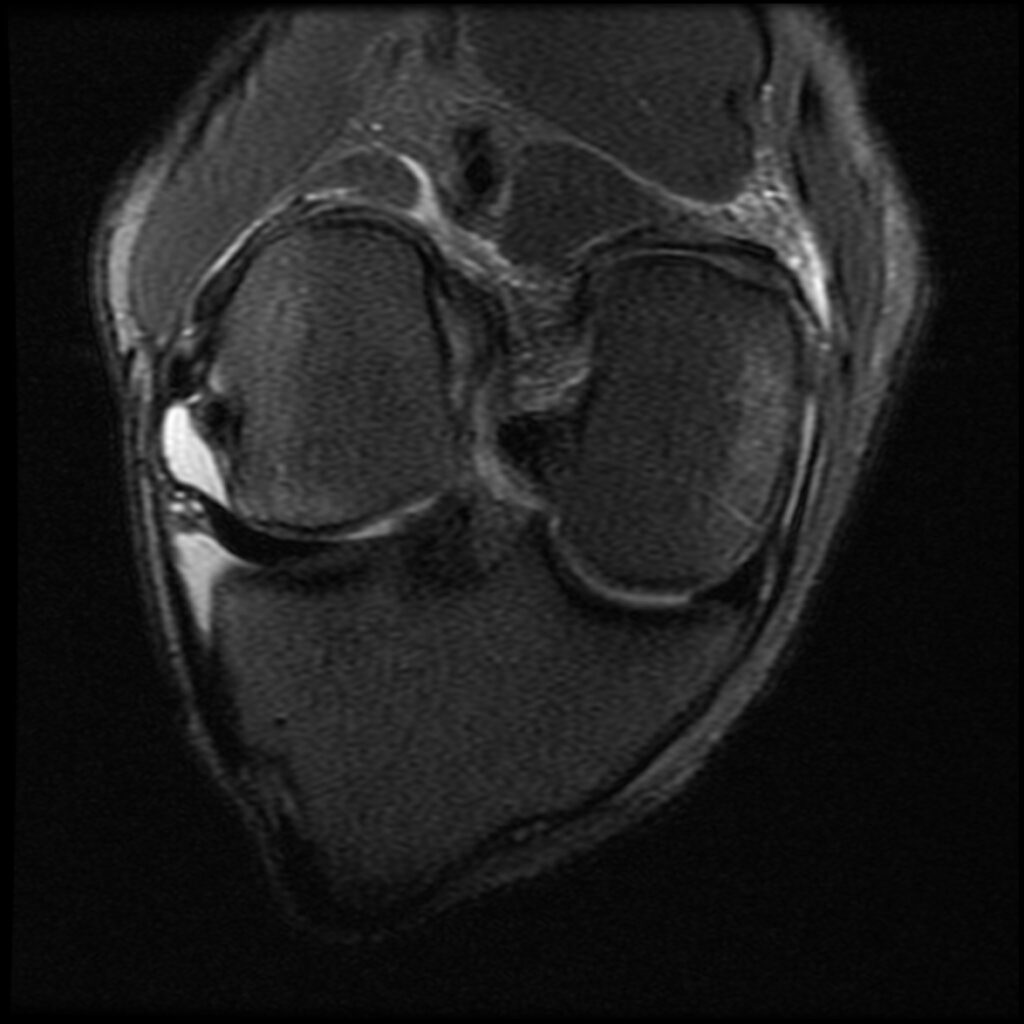

Patient D, age 19, sustained a competitive tumbling injury that involved a hard landing with the pathognomonic plant and pivot that directly tractions the ACL along its doubly obliqued path. The first MR scan was done the day after the trauma. She was initially treated 5 days post-injury. Her knee effusion was completely aspirated, then replaced with 3cc of autologous platelet-rich plasma and 5cc of platelet-poor plasma. Using ultrasound guidance, the ACL origin at the posterior femur was treated after carefully avoiding the vasculature and nerves. She was then instructed not to bear weight for 3 days, then use crutches/assisted weight bearing for 2 weeks. She was then to use a compression knee sleeve during sports or exercise. At her follow-up visit at 4 weeks, she was still having some instability at times and lateral knee pain. Her knee was evaluated with an ultrasound, and any areas of pathology seen were treated with hypertonic dextrose injection and needling technique. This included her medial and lateral collateral ligaments, and the patellar tendon and ligament. At 12-week follow-up, she continued to have some minor issues with her knee, so another evaluation and treatment were performed with hypertonic dextrose to the injured ligament and tendon areas found on the ultrasound examination. We obtained a new MR for her 16-week follow-up and noticed the ACL had re-ligamentized, and she reported full function and return to exercise. At 5-year follow-up, she claimed she was fully active, pain-free, but no longer tumbling.

Patient D Before

Patient D After